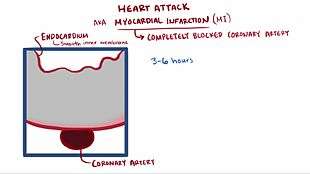

Acute myocardial infarction refers to two subtypes of acute coronary syndrome, namely non-ST-elevated and ST-elevated MIs, which are most frequently (but not always) a manifestation of coronary artery disease.[54] The most common triggering event is the disruption of an atherosclerotic plaque in an epicardial coronary artery, which leads to a clotting cascade, sometimes resulting in total occlusion of the artery.[55][56] Atherosclerosis is the gradual buildup of cholesterol and fibrous tissue in plaques in the wall of arteries (in this case, the coronary arteries), typically over decades.[57] Bloodstream column irregularities visible on angiography reflect artery lumen narrowing as a result of decades of advancing atherosclerosis.[58] Plaques can become unstable, rupture, and additionally promote the formation of a blood clot that occludes the artery; this can occur in minutes. When a severe enough plaque rupture occurs in the coronary arteries, it leads to MI (necrosis of downstream myocardium).[55][56] It is estimated that one billion cardiac cells are lost in a typical MI.[59]

If impaired blood flow to the heart lasts long enough, it triggers a process called the ischemic cascade; the heart cells in the territory of the occluded coronary artery die (chiefly through necrosis) and do not grow back. A collagen scar forms in their place. Recent studies indicate that another form of cell death, apoptosis, also plays a role in the process of tissue damage following an MI.[60] As a result, the person's heart will be permanently damaged. This myocardial scarring also puts the person at risk for potentially life-threatening abnormal heart rhythms (arrhythmias) and may result in the formation of a ventricular aneurysm that can rupture with catastrophic consequences.

In the absence of ST elevation, diagnosis of MI is based on a blood test for biomarkers (usually troponin). This can take 3–6 hours after the onset of symptoms to become positive. The scenario is referred to as "non-ST elevation acute coronary syndrome" (NSTEACS). In the meantime, the calculated risk of further cardiovascular events (e.g. using the GRACE score) and the presence of other ECG changes and clinical features determines ongoing management.[73][77]